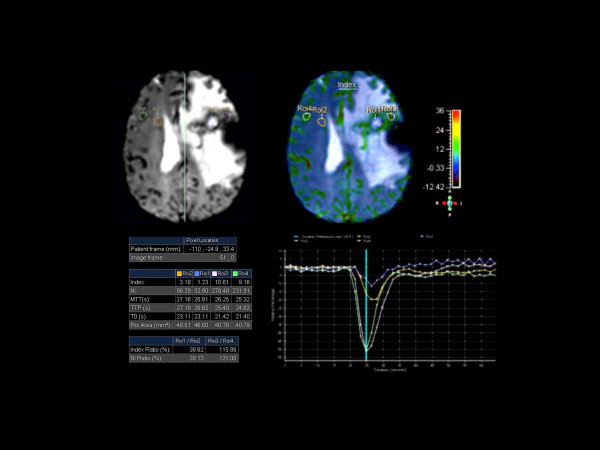

Axial T2* Perfusion